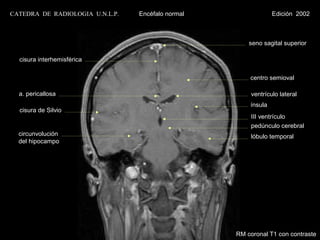

CATEDRA DE RADIOLOGIA U.N.L.P.   Encéfalo normal                Edición 2002

seno sagital superior

cisura interhemisférica

centro semioval

cuerpo calloso

ventrículo lateral

cisura de Silvio                                     ínsula

III ventrículo

fosa interpeduncular                                 pedúnculo cerebral

lóbulo temporal                                      circunvol. del hipocampo

V par

c.a.i.

c.a.e

.

RM coronal T1 con contraste